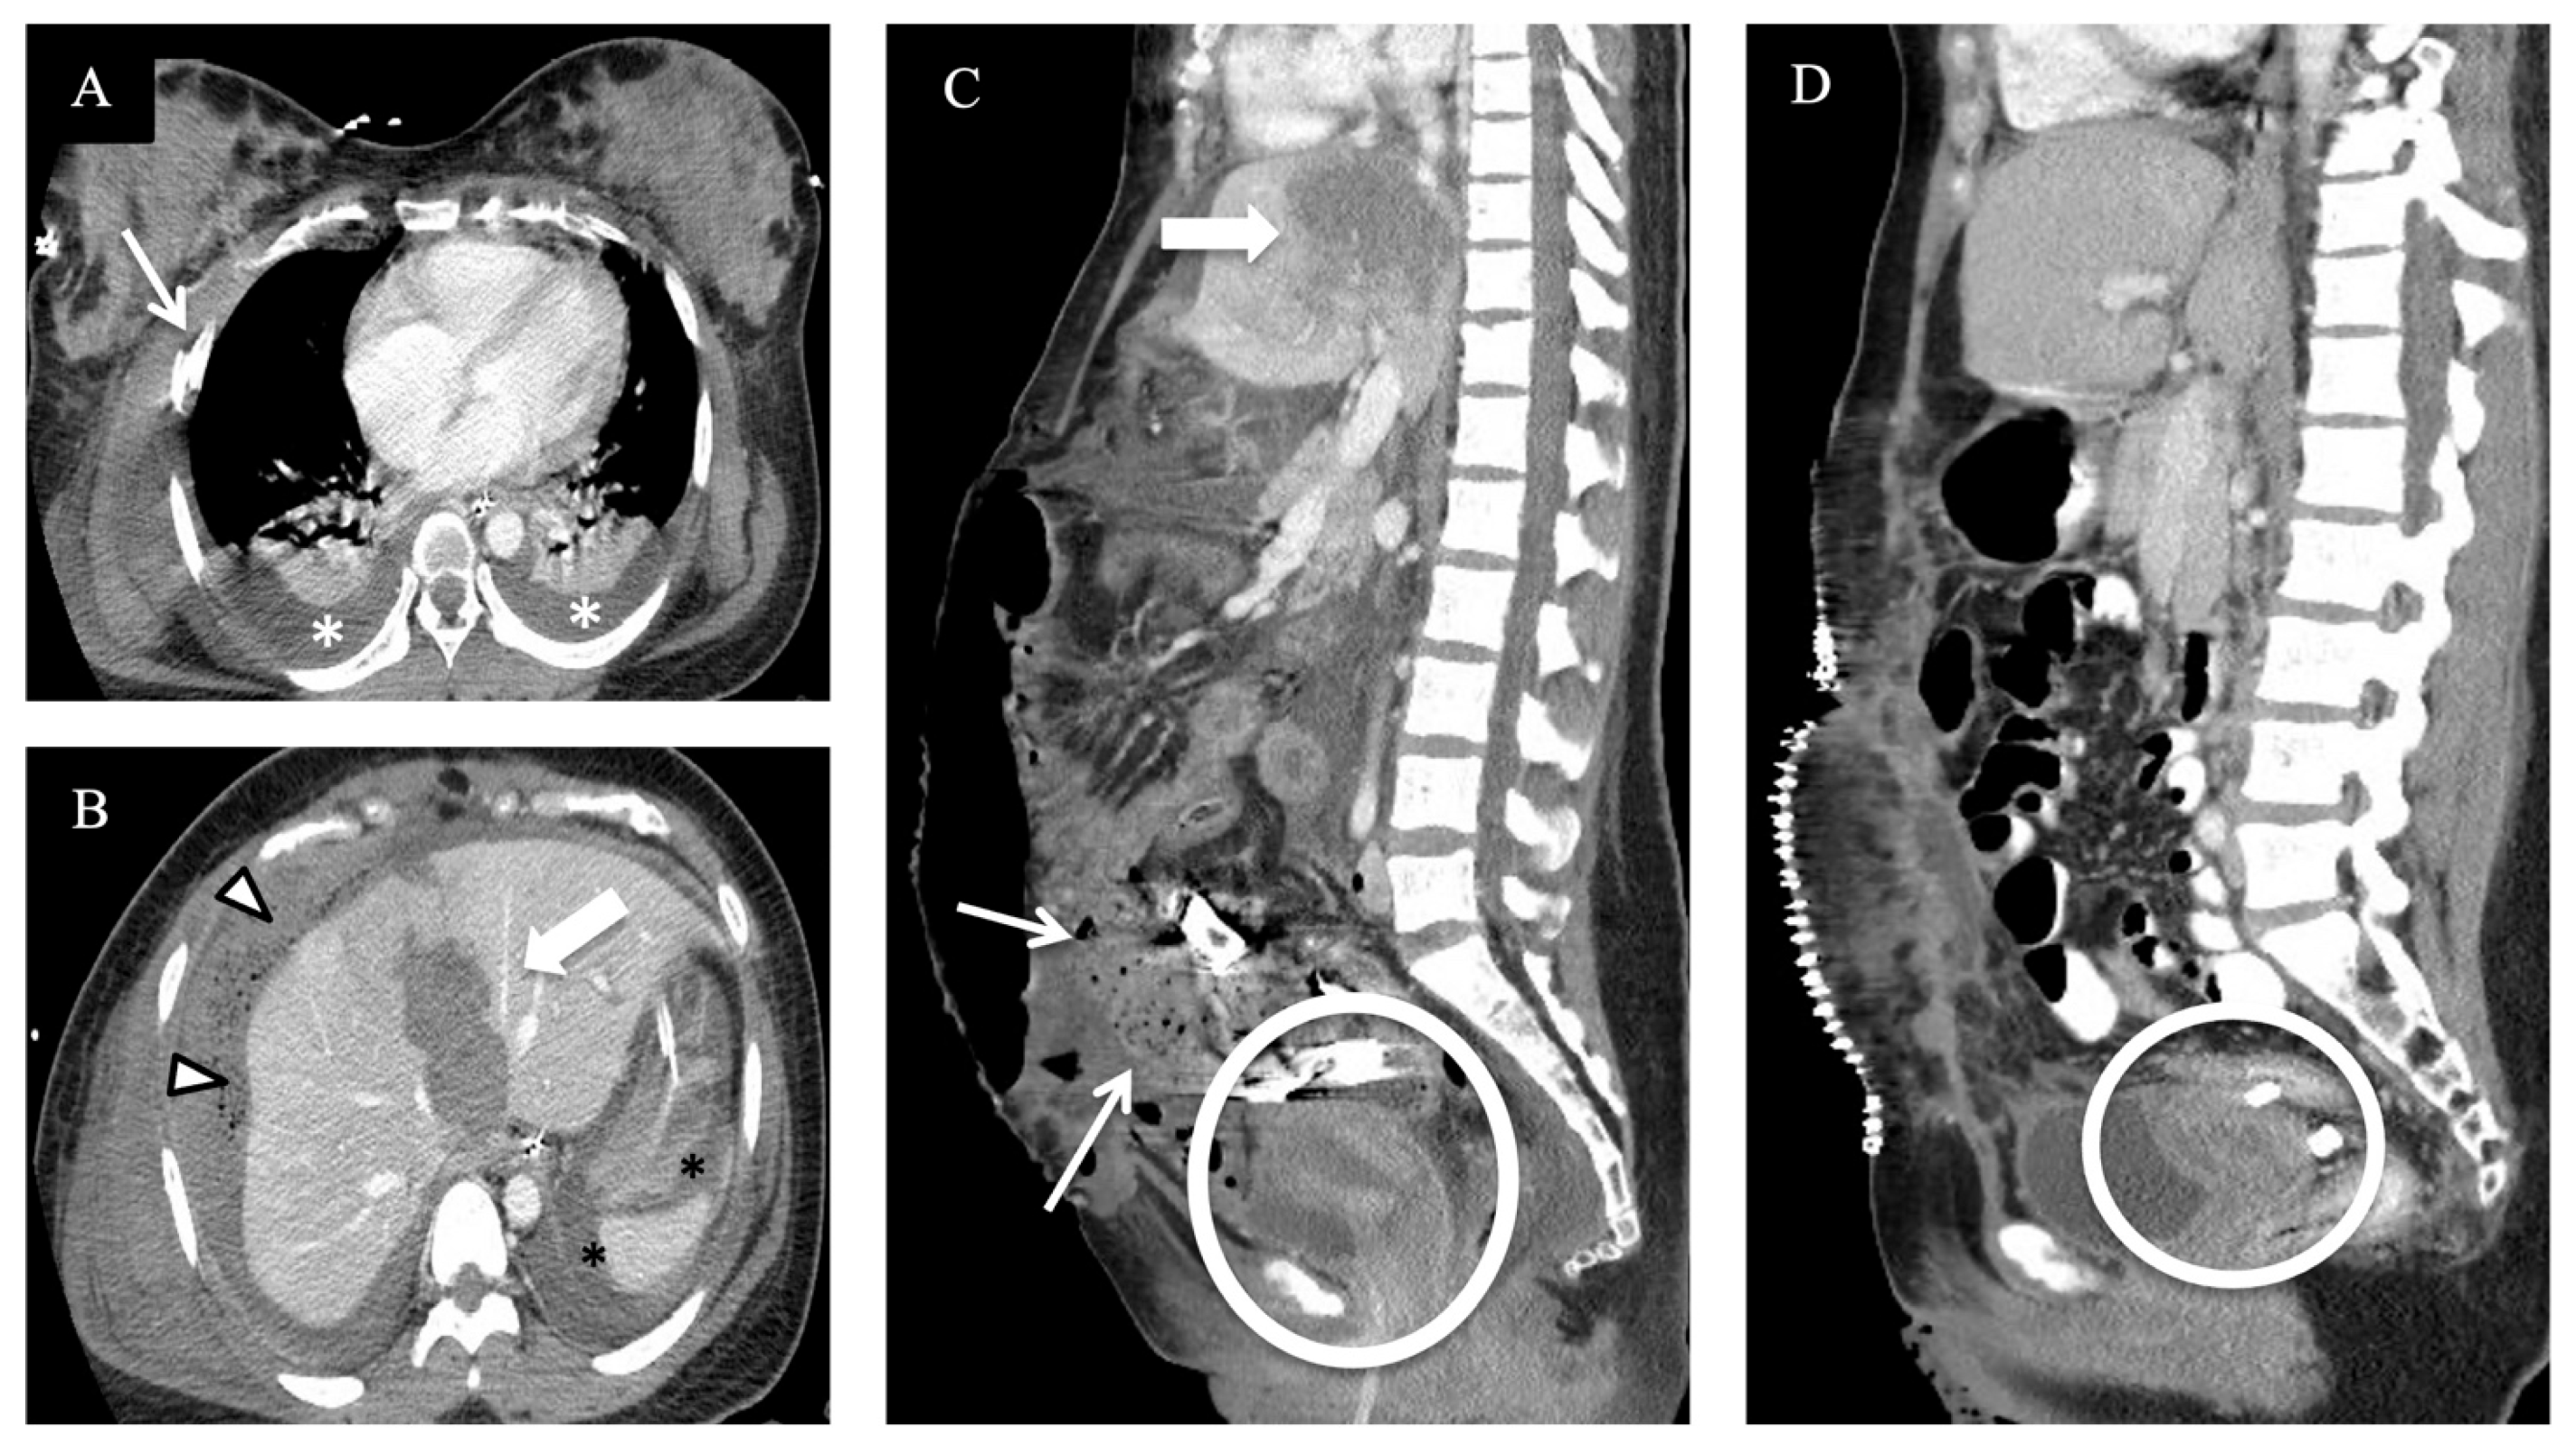

4. Review of Local Presentations